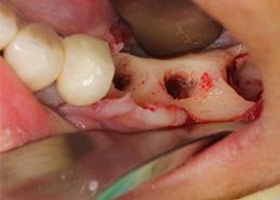

4. 移除感染之植體,解決吸收植體牙周發炎。

![proimages/case/Artificial_implant/save-defeat03-1.jpg proimages/case/Artificial_implant/save-defeat03-1.jpg]()